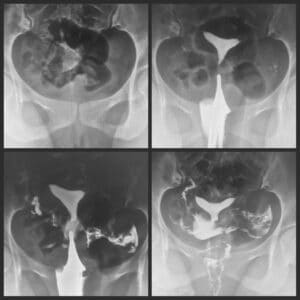

Hysterosalpingography(هیستروسالپنگوگرافی)برای بررسی حفره ی رحم و لوله های رحمی انجام می شود.

معمولاً در مواردی كه بیمار دچار ناباروری یا سقط های مكرر می شوند انجام می گیرد.

چسبندگی های درون رحمی، پولیپ، فیبروم، انسداد لوله ها.

همچنین برای ارزیابی لوله های فالوپ شامل:

1) انسداد

2) بستن به دنبال عقیم سازی و باز شدن مجدد آن

توسط Hysterosalpingography( هیسترو سالپنگوگرافی ) قابل برسی است.

Hysterosalpingography( هیسترو سالپنگوگرافی ) اطلاعات با ارزشی از هر گونه ناهنجاری كه سبب ناباروری می شود می دهد.

گاهی اوقات باعث باز شدن لوله های مسدود شده می شود و بالا بردن احتمال حامله شدن را به در پی دارد.

بیمار در وضعیت لیتوتومی قرار می گیرد. در شرایط استریل یك اسپكولوم در واژن قرار می گیرد . دهانه ی رحم ضدعفونی می شود. پس از قرارگیری كاتتر یا كانولاو تناكولوم. داروی حاجب به میزان3 cc (در شرایطی كه بیمار بارداری قبلی داشته یا زایمان طبیعی داشته 5 cc یا بیشتر) تزریق می شود.

یك گرافی انجام می شود . تزریق بعدی بین 6تا cc10 تزریق می شود. پس از آن گرافی تأخیری و P.V.C گرفته می شود.